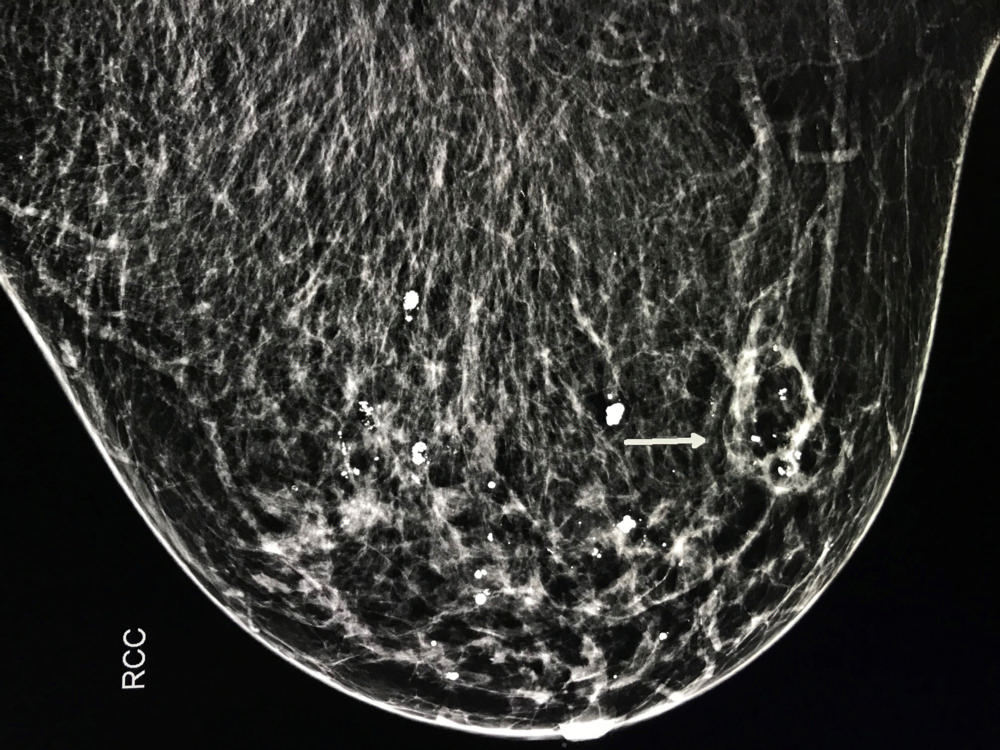

Figure 6. Mammogram demonstrates cancer in right breast prior to cryoablation (arrow).

High-res (TIF) version